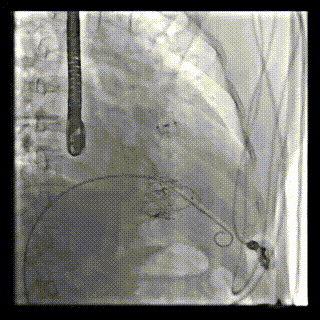

本周三例接受LuX-Valve Plus經(jīng)血管三尖瓣置換術(shù)的患者中,第一例患者為冠狀動(dòng)脈旁路移植術(shù)+Bentall+二尖瓣成形術(shù)后;第二例患者為永久起搏器植入術(shù)后,存在跨三尖瓣導(dǎo)線;第三例患者合并房顫、房缺及左心耳封堵術(shù)后。

三例患者入院后,葛均波院士團(tuán)隊(duì)周達(dá)新教授、潘文志教授、張?jiān)床┦?、陳莎莎博士及心超室的潘翠珍教授、李偉教授?duì)患者的情況進(jìn)行詳細(xì)評(píng)估和討論,最終決定為三例患者選擇LuX-Valve Plus40mm、50mm和50mm型號(hào)的瓣膜進(jìn)行手術(shù)治療。手術(shù)后即刻拔除氣管插管,術(shù)后患者三尖瓣反流癥狀得到顯著改善,復(fù)查心超結(jié)果顯示人工三尖瓣瓣膜支架固定穩(wěn)定,瓣葉關(guān)閉形態(tài)未見異常,未見明顯反流。